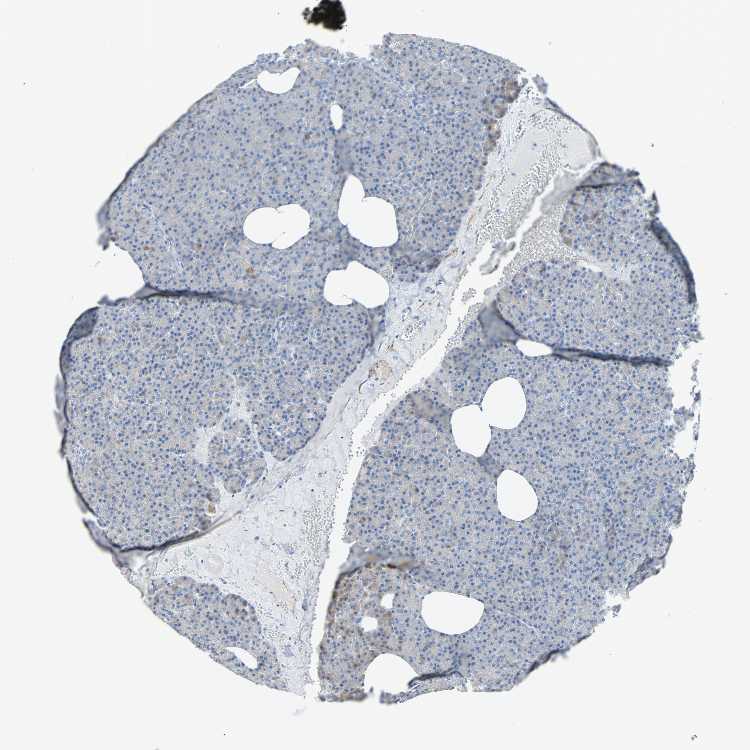

PANCREAS - Antibody stainingi

Antibody staining in the annotated cell types in the current human tissue is reported as not detected, low, medium, or high, based on conventional immunohistochemistry profiling in selected tissues. This score is based on the combination of the staining intensity and fraction of stained cells.

Each image is clickable and will lead to virtual microscopy that enables deeper exploration of all samples and also displays staining intensity scores, fraction scores and subcellular localization as well as patient and tissue information for each sample.

Antibody HPA007534Antibody CAB008376

Exocrine glandular cells Not detectedNot detected

Pancreatic endocrine cells -Not detected